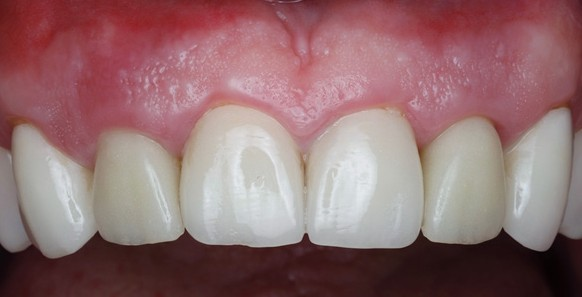

Once the temporary is picked up and emergence profile is customized to have an adequate regenerative space and properly placed Critical contour (0.5 short of the final gingival margin) we are ready to deliver the prosthesis.

Prior to delivery make sure to leave a good amount of room in the embrasures to allow for soft tissue fill during the training period.

Upon delivery of the prosthesis, some blanching is a good sine of tissue compression in needed areas (usually proximally) which starts the process of tissue training.

After 3 months of tissue training, patient returned for his final evaluation prior to final restoration.